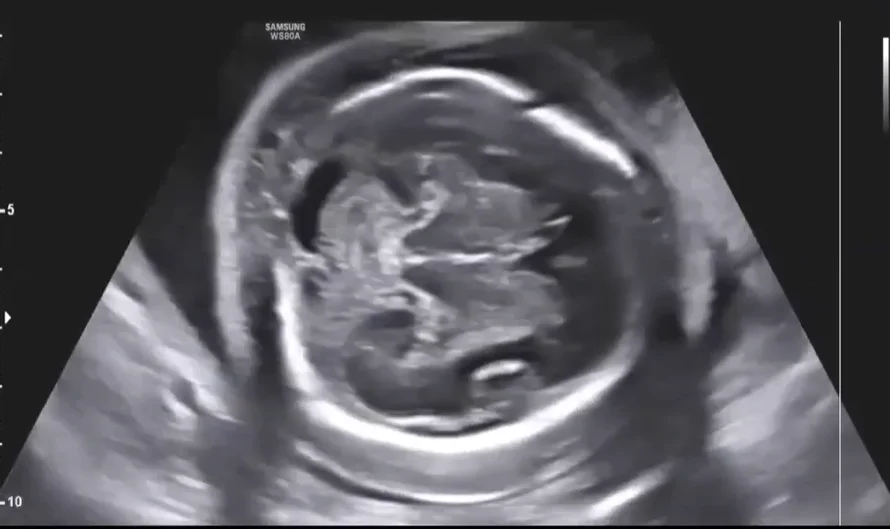

• Sinh trắc học thai nhi (Fetal Biometry)

• Thai chậm tăng trưởng trong tử cung (Fetal Growth Restriction - FGR)